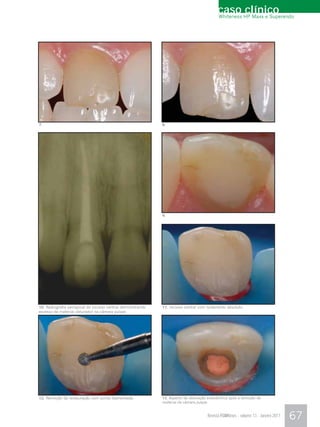

66       Reconstrução Estética em Dente Anterior: da

Alternativa menos Invasiva à mais Invasiva